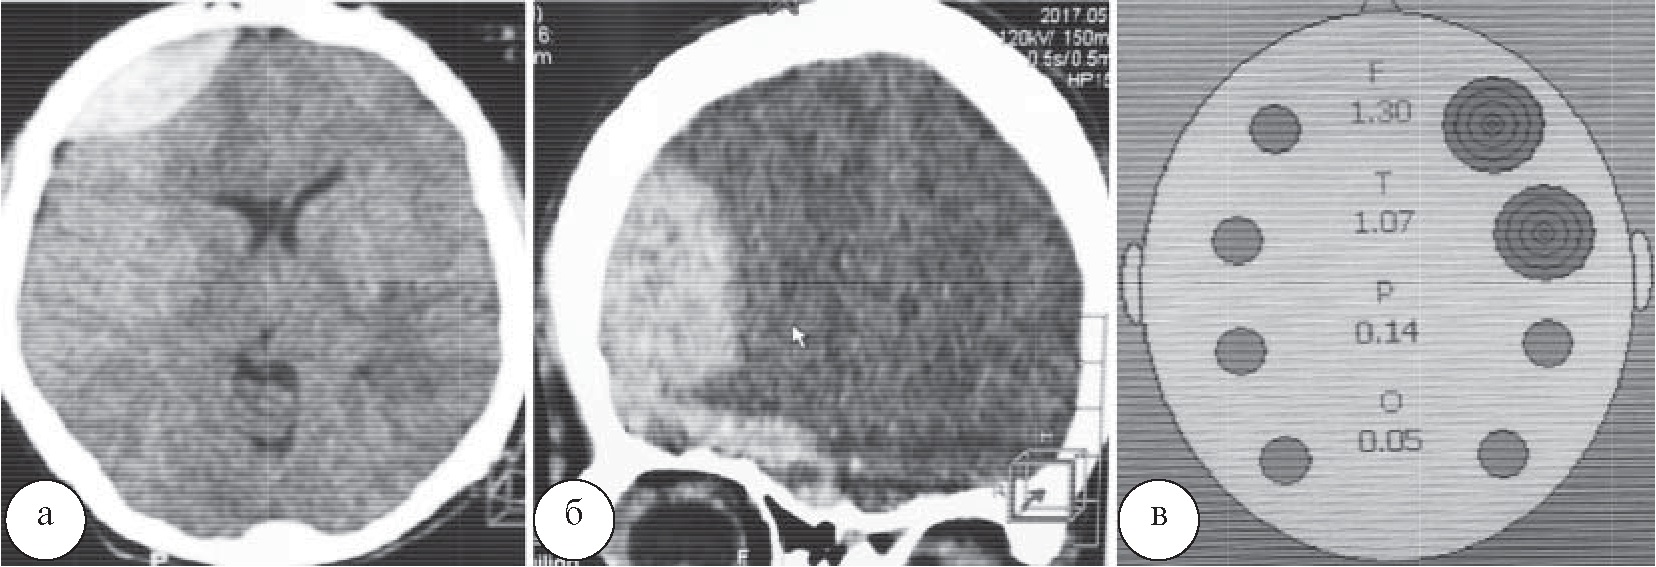

Результаты и их обсуждение. При обследовании трех пострадавших с изолированными ЧМТ у одного из них, по данным ИСГ, были выявлены признаки внутричерепной гематомы. При выполнении КТ у данного пострадавшего была диагностирована эпидуральная гематома в правой лобной области, совпадавшая с результатами ИСГ, свидетельствовавшими о наличии патологии в правой лобной области (рис. 3). В двух наблюдениях изменения по результатам ИСГ и КТ отсутствовали.

Рис. 3. Эпидуральная гематома правой лобной области, СКТ: а – сагиттальный срез; б – фронтальный срез; в – результаты ИСГ

При обследовании пациентов с сочетанными ЧМТ в 21 случае внутричерепных гематом по данным ИСГ и по данным КТ головы не выявлено. В 6 наблюдениях отмечен ложноположительный результат, при этом данными КТ наличия внутричерепной гематомы не подтверждено. Выявленные ложноположительные результаты ИСГ у 2 пациентов были связаны с наличием подкожных гематом в зоне сканирования, у 4 пациентов с наличием сгустков крови и кровотечения из ран волосистой части головы в исследуемых областях.